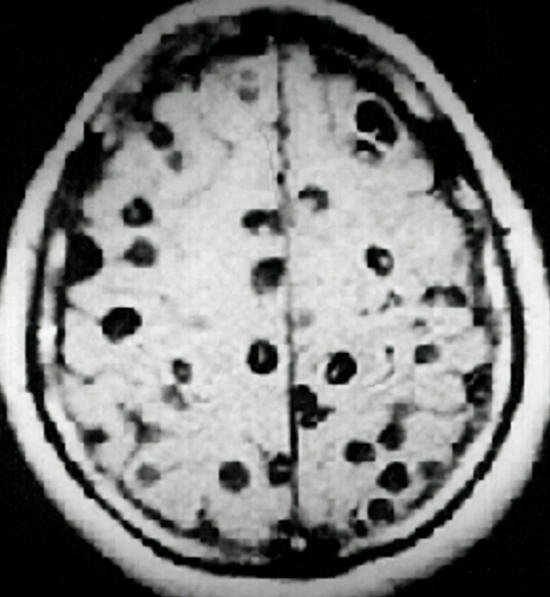

除此之外,绦虫在人体内随时能侵入皮肤和大脑,使人患上严重的皮肤疾病和精神病。但即便如此,减肥减到疯魔的英国女性,在了解到绦虫的危害后,依然以身犯险地尝试。

绦虫侵入大脑图